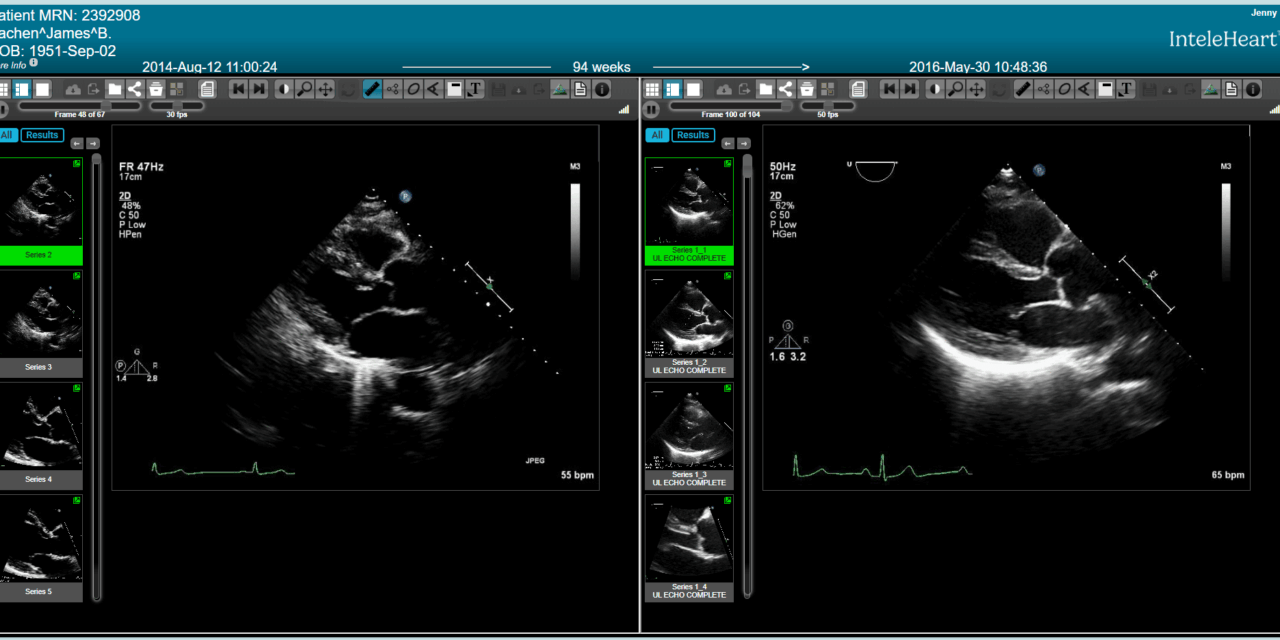

Photo caption: InteleHeart

Photo credit: Intelerad